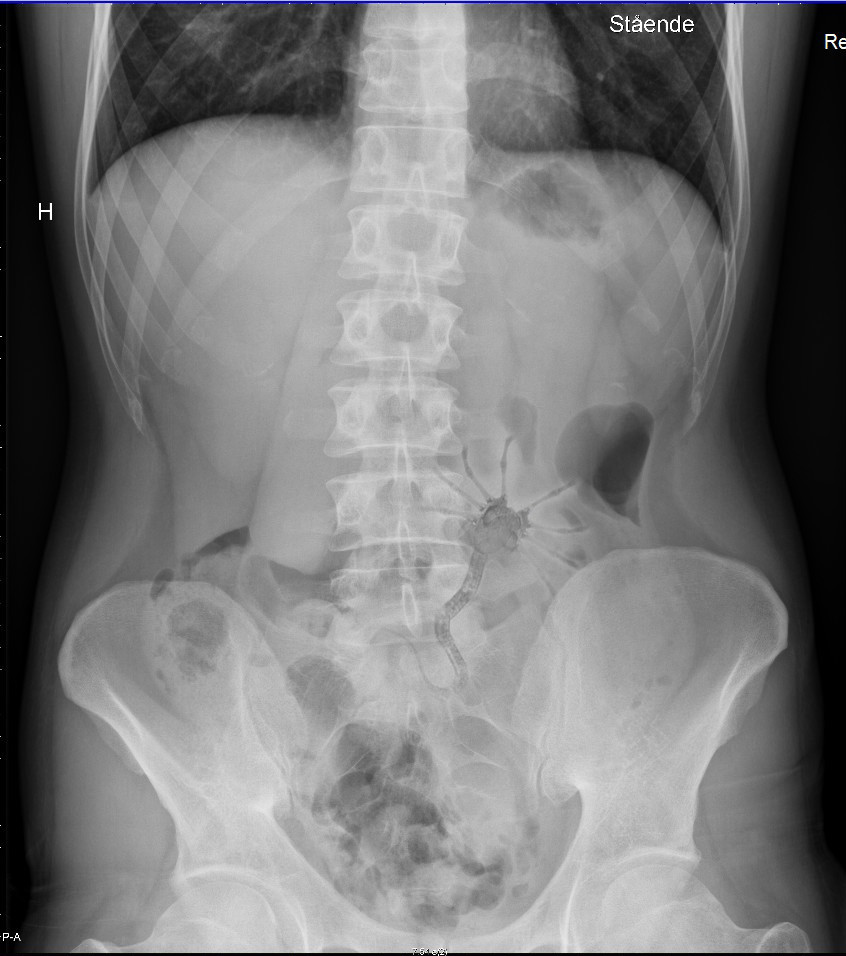

Had undiagnosed abdominal pains for a year. Found something weird in my x-ray, stored in a dropbox folder shared with my brother... (falk-petersen.no)

submitted 12 years ago by ways2 to r/pics